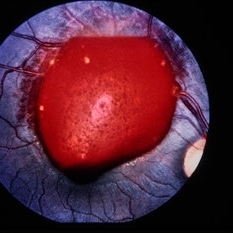

Choroidal rupture with fresh hemorrhage

Condition/keywords: trauma